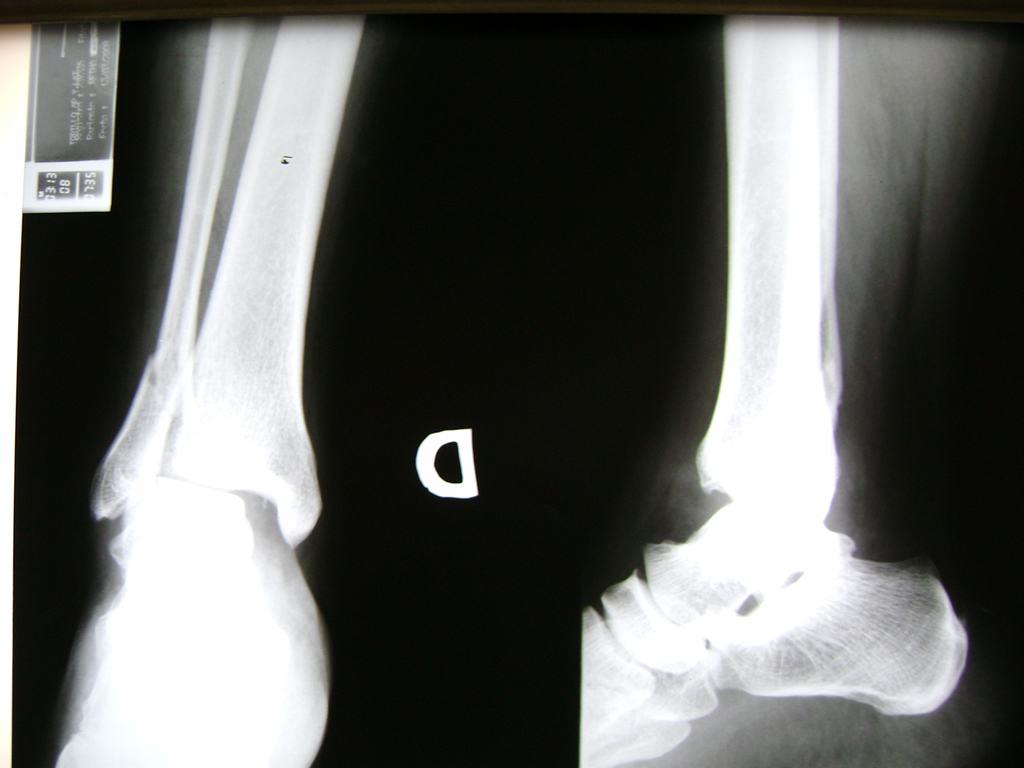

Una fractura de tobillo es la rotura de uno o más de los huesos del tobillo. Estas fracturas pueden ser:

- Parciales (el hueso está sólo parcialmente fisurado, no del todo).

- Completas (el hueso está perforado y está en 2 partes).

Algunas fracturas de tobillo pueden requerir cirugía si:

- Los extremos de los huesos están desalineados entre sí (desplazados).

- La fractura se extiende hasta la articulación del tobillo (fractura intra-articular).